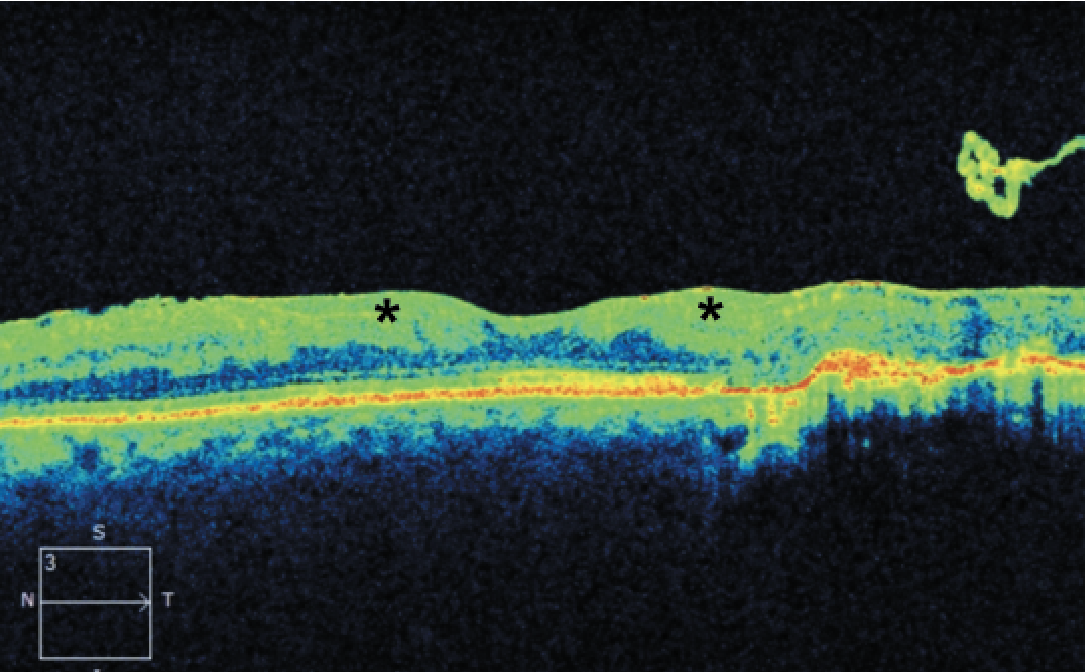

| Figure 1. Optical coherence tomography of a 41-year-old male with a history of proliferative diabetic retinopathy demonstrating disorganization of the retinal inner layers (asterisks). |

More specific pathologic changes such as disorganization of the retinal inner layers (DRIL; Figure 1) can be appreciated only through OCT and have been identified as markers of visual potential and predictors of DR progression.4 Similarly, outer retinal disruption (Figure 2) and early photoreceptor damage may indicate more advanced disease with poor visual prognosis.5